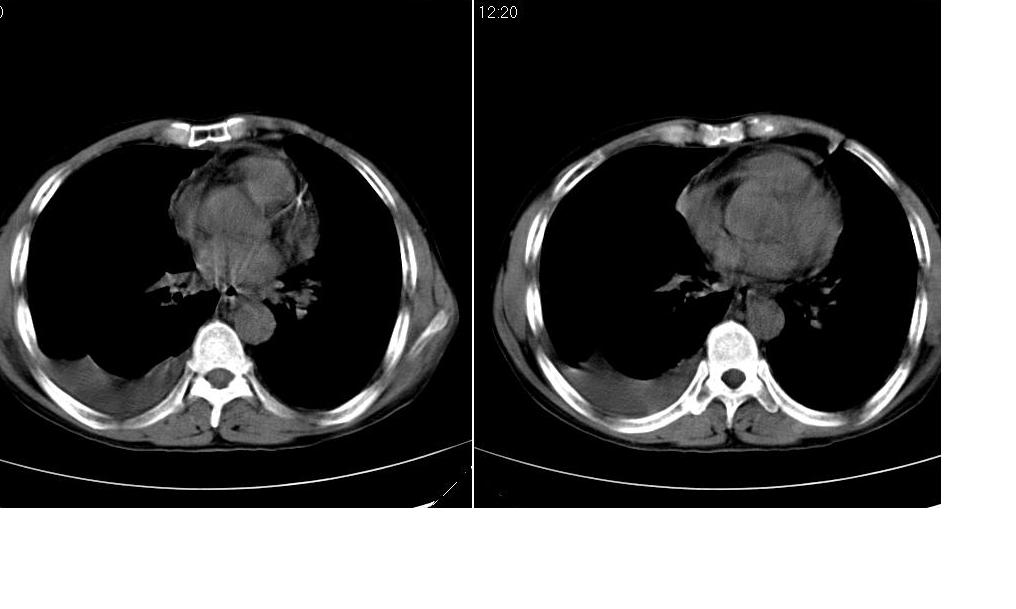

考虑:1、右肺下叶中心型肺癌并纵隔淋巴结转移。胸腔积液。

2、心包少量积液。

3、左肺改变不除外癌性淋巴管炎或化疗后肺间质纤维化。

1 右肺下叶中心型肺癌.纵隔内淋巴结转移.右侧胸腔积液. 2 心包少量积液.3 肺间性改变考虑与化疗有关.